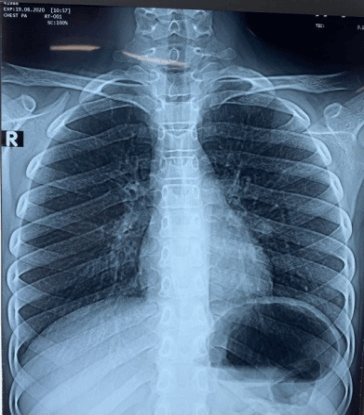

A 15-year-old boy came to the hospital with a history of gradually progressing left sided weakness of insidious onset for 6 months, low grade intermittent fever for 1 month and generalized headache with early morning exacerbation for 1 month. His physical examination revealed 100° F temperature, early stage papilledema, reduced power of all groups of muscles on the left side (MRC grade 3) with increased tone and exaggerated jerks in the left sided limbs and extensor planter response bilaterally. His gait was hemiplegic. His blood work showed raised ESR (22mm). Sputum for acid fast bacilli was negative. Chest roentgenogram showed a round hyperdensity near the left hilum with mild bilateral hilar patchy opacities (Figure 1).

Figure 1: Chest roentgenogram showed a round hyperdensity near the left hilum with mild bilateral hilar patchy opacities.